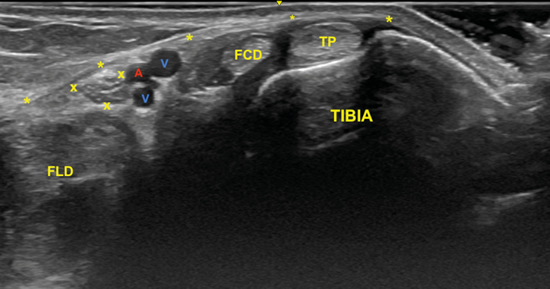

El nervio tibial, que se sitúa en superficie a las estructuras musculotendinosas y bajo la fascia crural, de forma habitual está dispuesto posterior a los vasos tibiales posteriores (Figura 6).

Figura 6. Túnel tibiocalcáneo. El examen en eje corto, bajo la fascia crural (*) y de anterior a posterior, muestra el tendón tibial posterior (TP), el tendón flexor largo de los dedos (FCD) aún con fibras musculares, y el músculo flexor largo del primer dedo (FLD). Entre estas dos estructuras se encuentra el haz neurovascular que está formado por las venas (V), la arteria (A) tibial posterior y por el nervio tibial (rodeado por X).

El nervio tibial tiene forma más o menos redondeada, patrón fibrilar con zonas punteadas anecogénicas e hiperecogénicas que corresponden a los haces nerviosos y al tejido conectivo de sostén, la típica imagen denominada de “sal y pimienta”, y sección transversal entre 10 mm26 y 12,7 mm27 a nivel del maléolo tibial (Figura 7).